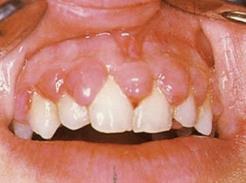

17.1. ábra. Cyclosporin-A okozta ínyhyperplasia vesetranszplatált betegen

A cyclosprin-A használata a szervkilökődés legbiztosabb szere annak ellenére, hogy parodox módon nefrotoxikus anyag. A legfontosabb orális mellékhatás az ínyhyperplasia (17.1. ábra). Ma már vannak alternatív szerek, mint pl. tacrolymus, amelynek azonban hasonló mellékhatásai vannak.

Ilyen ínyelváltozás a vesetranszplantált esetek 30%-ánál alakul ki. A vese eredetû magas vérnyomás kezelésére alkalmazott Ca-csatorna-blokkolók (niphedipin, verapamil, amilodipin származékok) mellékhatása ínyhyperplasia, így azt a transzplantáció után az elkerülhetetlenül alkalmazandó cyclosporin még tovább súlyosbíthatja Sok esetben vesetranszplantáció után is a két szert kombinációban

kapja a beteg, így a kétszer mellékhatása összegződik. Míg a kalciumcsatorna-blokkolók más hatásmechanizmusú vérnyomáscsökkentő szerrel helyettesíthetők, ma még a cyclosporinnak nincs valódi alternatívája. Sokszor kombinálják a cyclosporint kortikoszteroidokkal, és a szteroidkezelésben részesülő vesetranszplantált betegek érzékenyek bakteriális, gombás és vírusfertőzésre is, gyakran alakult ki náluk malignus orális tumor. Malignus orális tumort azonban már leírtak cyclosoprin-A-val kezelt betegeken is.